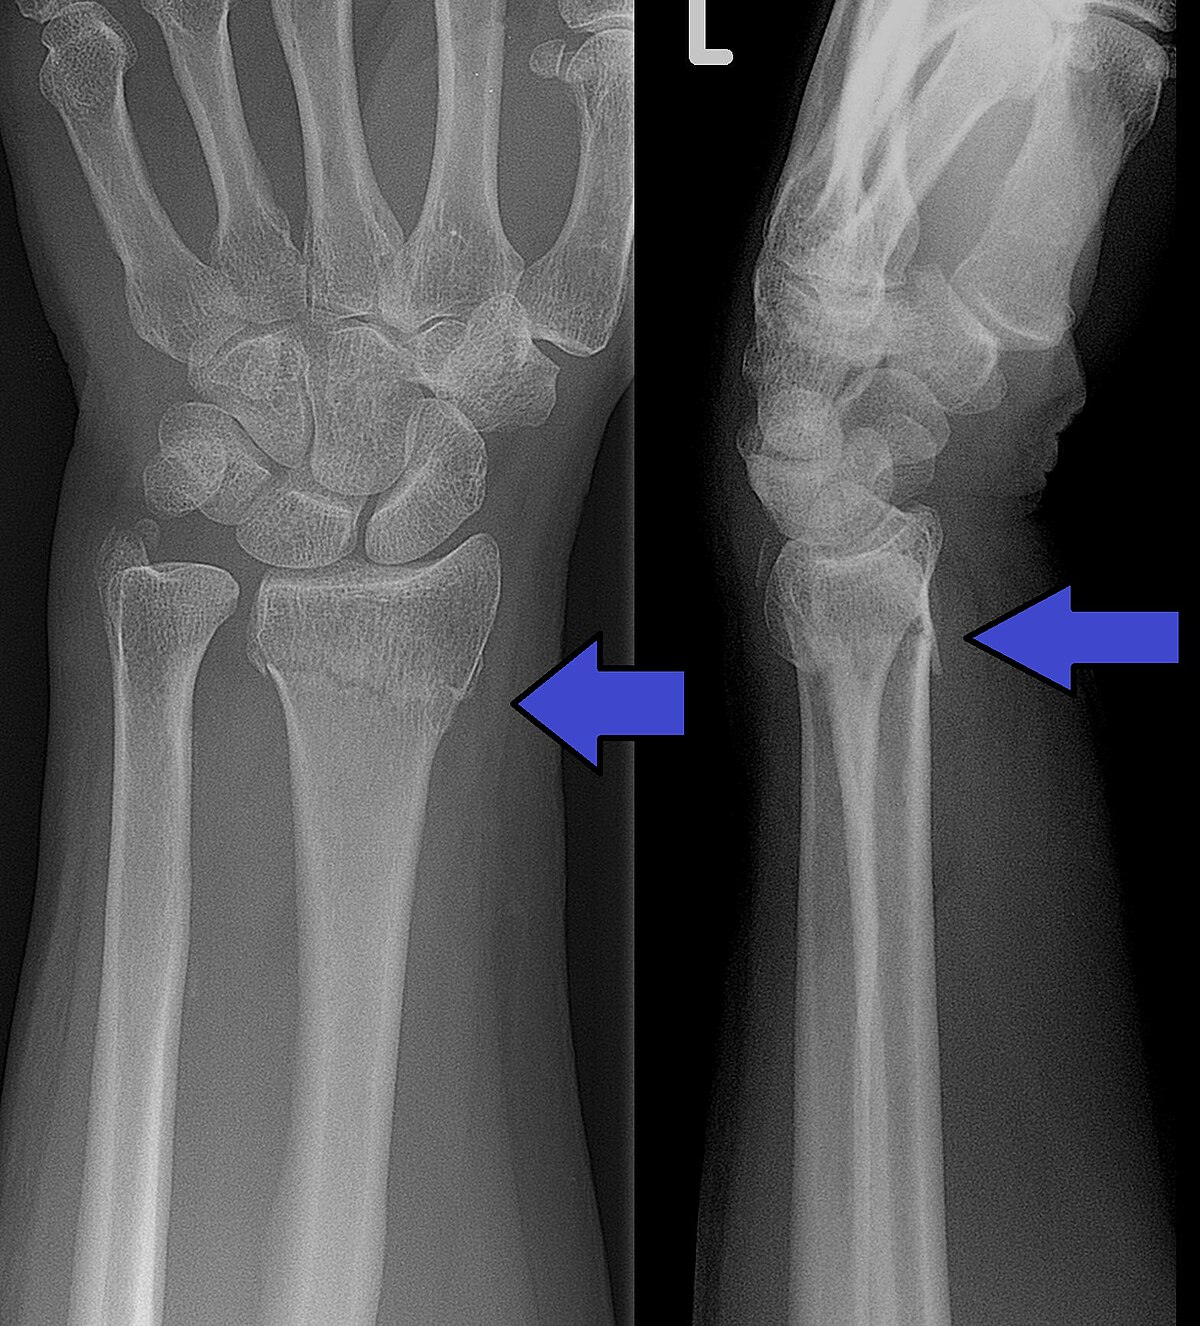

63 year old female:

acute pain and swelling in her distal forearm after falling on her outstretched hand.

History:

postmenopausal

bone mineral density from forearm indicated osteoporosis

Physical Examination:

deformity of distal forearm

posterior displacement of distal radius

Acute tenderness and swelling of distal forearm/wrist

Paraesthesia over lateral palm /digits & weakness in thumb opposition

Radiolucent distal radius fracture with posterior and medial displacement

colles fracture

common extra-articular fracture

bone break that does not involve the articular surface (the surface of the bone that forms part of a joint)

occurs as a result of a fall on an outstretched hand

posterior displacement

medial angulation of the distal radius (tilting of the distal fragment of the radius bone toward the ulna)